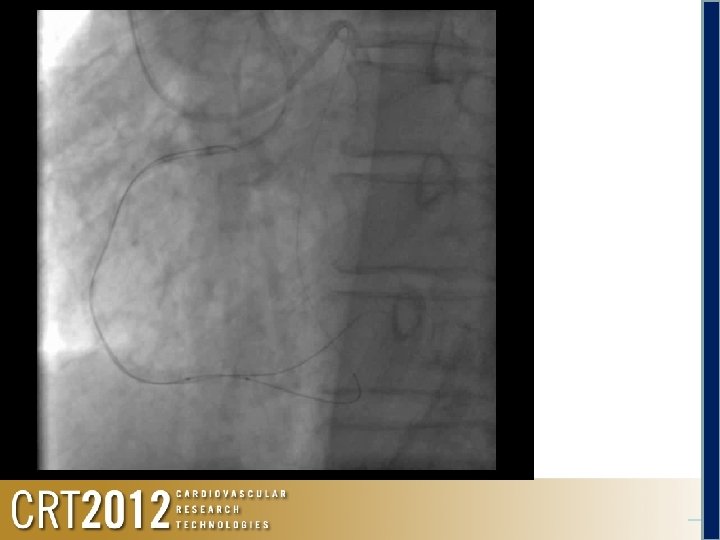

Angio LCA Retrograde Via the Rt. radial 6 F EBU 3. 5

Selection of the Septal Channel

Retrograde Corsair + Fielder FC